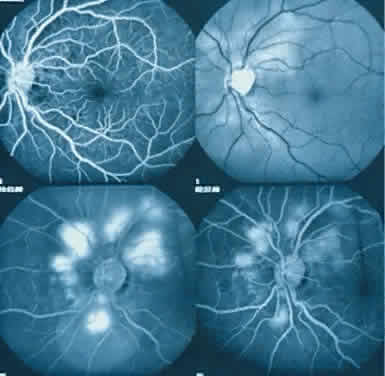

The ocular manifestations of antiphospholipid antibodies include retinal venous and arterial occlusions, amaurosis fugax, diplopia, and visual field loss.34,35 Extensive vasoocclusion, neovascularization, and vitreous hemorrhage may occur (Fig. 3). Treatment consists of photocoagulation for the neovascularization and systemic anticoagulation and immunosuppression. Vitrectomy may be required for vitreous hemorrhage. The role of systemic treatment of lupus anticoagulant in the management of ocular disease is unclear. Some investigators suggest that systemic anticoagulation be started promptly.36 The optimal duration of anticoagulation and whether antiplatelet therapy should be used are not known however. The optimal use of corticosteroids or other immunosuppressive drugs such as cyclophosphamide and azathioprine also is unknown. Two reports have found an association with the antiphospholipid syndrome and some additional retinal conditions. One report also has associated the primary antiphospholipid syndrome with central serous chorioretinopathy.37 In addition, lupus anticoagulant positivity could represent an additional risk factor for diabetic retinopathy according to a recent report.38